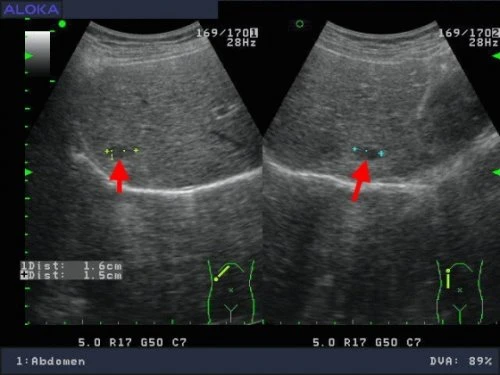

正常肝臟![]() Rt liv :右葉肝臟 IVC :下腔靜脈 hepatic V :肝靜脈 ![]() Lt liv :左葉肝臟 , LHV :左側肝靜脈 , LPV :左側肝門靜脈 , IVC :下腔靜脈 , SMA :上腸繫膜動脈 , SV :脾靜脈 , P :胰臟 , AORTA:主動脈 肝癌 ![]() 肝硬化合併早期肝癌1.4公分 ![]() 轉移性肝癌 ![]() 肝癌局部復發 1.6 公分 ![]()